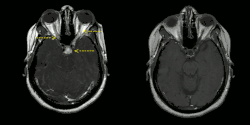

Left image: MRI findings (T1-weighted images) in a patient with neurosacoidosis showing thickening of infundibulum and both optic nerves (white signal marked with yellow arrows; width 6 mm).

Right image: MRI brain with contrast showing near resolution of enhancement after treatment.